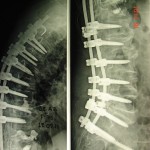

Εικόνα 2: α, β, γ

Αξονική τομογραφία της σπονδυλικής στήλης (οβελιαία λήψη). Παρατηρείται καθίζηση σπονδυλικών σωμάτων, συνέπεια της οστεοπορώσεως.